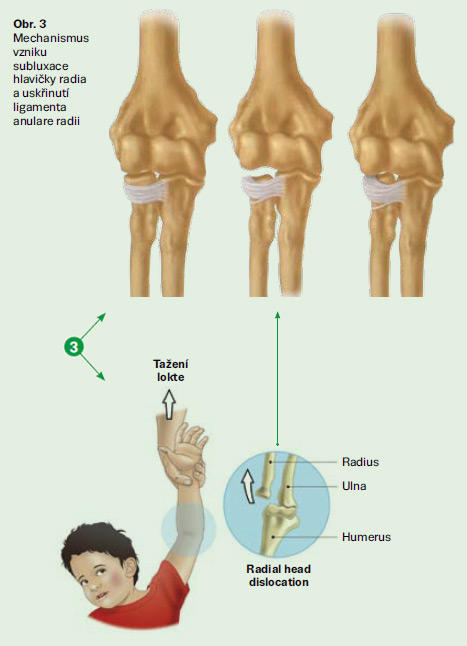

Pronatio dolorosa (lat. bolestivá pronace, Chassaignacova obrna) je bolestivé držení lokte u malých dětí, vzniklé po prudkém tahu a rotaci ruky, při kterém dochází k subluxaci hlavičky radia v lokti s uskřinutím lig. anulare. Nejčastěji vzniká u dětí mezi 2. a 4. rokem při tahu za zápěstí či předloktí např. vytahováním dítěte za jednu horní končetinu vzhůru, zejm. při zabránění pádu. Patří k nejčastějším úrazům malých dětí.

Pronatio dolorosa je méně závažné, ale časté poranění, které vzniká při násilném tahu za pronované a hyperextendované předloktí, kdy ligamentum anulare radii (vřetenní prstencový vaz) sklouzne přes hlavičku radia a uskřine se mezi hlavičku radia a capitulum humeri (do radiohumerálního kloubu). Vzniká nejčastěji tak, že dítě vedené za ruku padá a rodič ve snaze zabránit pádu ho prudce zatáhne za ruku. Tělo dítěte rotuje kolem ruky a působí celou vahou na loketní kloub. Dále může vzniknout při manipulaci s nespolupracujícím dítětem či při hře, kdy starší kamarád nebo člen rodiny točí (pohupuje) dítětem za jeho ruce či předloktí.

Vazy malých dětí ještě nejsou plně vyvinuty, proto i malá síla působící na kloub může způsobit jeho posunutí nebo částečné vykloubení. Částečně je to dáno i mechanismem poranění, který staví tuto věkovou skupinu do rizikové skupiny – batolata často chodí ruku v ruce s vyšším dospělým či starším dítětem. Je zde ale i anatomická predispozice k subluxaci hlavičky radia u dětí mladších šesti let. Jak děti rostou, jejich kosti se postupně zpevňují a vazy sílí, což pomáhá udržet loket pevně v místě, a proto je riziko subluxace hlavičky radia u dětí starších pěti či šesti let méně pravděpodobné. Dívky jsou více ohroženy než chlapci, a rovněž levá paže bývá častěji postižena (pravděpodobně z toho důvodu, že většina rodičů jsou praváci, a tudíž drží dítě za levou ruku). Měkké tkáně nebývají postiženy. Ligamentum anulare radii může být u některých malých dětí obzvlášť uvolněné, což může vést k opakovaným subluxacím hlavičky radia. Subluxace hlavičky radia je jen zřídka způsobena pádem (při něm hrozí spíše zlomeniny). Tento úraz je vzácný v mladším dospělém věku.